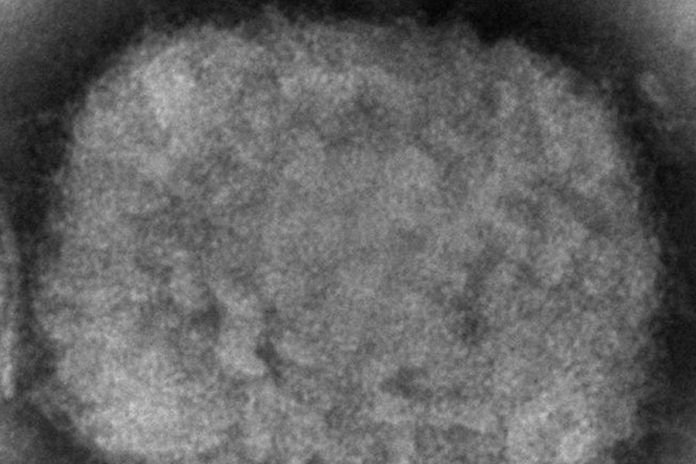

Nueva York, EE.UU. — Massachusetts reportó el miércoles un raro caso de viruela símica en un hombre que viajó recientemente a Canadá, y los funcionarios de salud están revisando si está relacionado con pequeños brotes en Europa.

La viruela símica suele limitarse a África, y los raros casos que se dan en Estados Unidos y otros países suelen estar relacionados con viajes a ese continente. Este mes se ha notificado un pequeño número de casos confirmados o sospechosos en Gran Bretaña, Portugal y España.

La viruela símica suele comenzar con una enfermedad similar a la gripe y una inflamación de los ganglios linfáticos, seguida de erupciones en la cara y el cuerpo. En África, la gente se ha infectado a través de las mordeduras de roedores o pequeños animales, y no suele propagarse fácilmente entre las personas.

La viruela símica pertenece a la misma familia de virus que la varicela. La mayoría de las personas se recuperan de la viruela símica en unas semanas, pero la enfermedad es mortal para hasta una de cada 10 personas, según la Organización Mundial de la Salud.